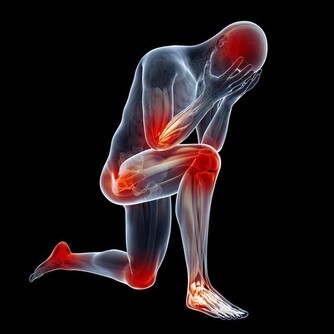

(圖片來源) 一位居住在倫敦的人的親身經歷 他去巴基斯坦開會的時候,突然胸口劇痛, 後來被醫院驗出來, 他的三條心血管已經被嚴重堵塞, 需要做搭橋手術。 手術的時間是一個月以後, 在這個期間,他去看一位治療師。 這位治療師給了他一個建議,結果卻十分驚人...! 食療一個月,心血管有驚人變化! 這位Hakim讓他自己在家中做食療,他吃了一個月。 一個月後他去同一家醫院做檢查, 發現三條血管幹乾淨凈, 原來堵塞的地方已經全通了。 為了讓更多的人受益, 他把自己的經驗放在網上分享, 他的前後兩張血管照片也放了在網上, 在照片中,服用食療之前與之後的分別, 連普通人也看得出來。